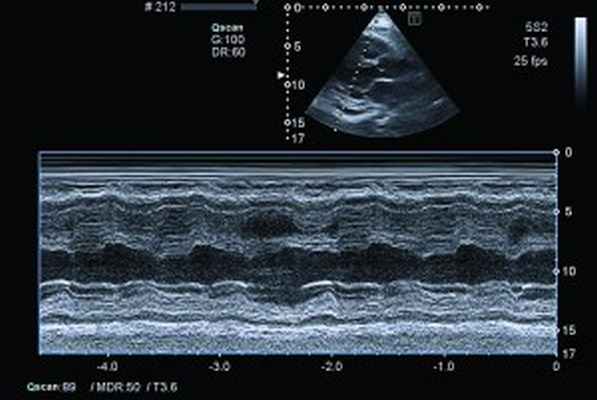

- Ультразвуковые исследования.ЭхоКГ выявляет утолщение в области верхушки сердца, которое ассоциируется с фиброзным процессом или тромботическими отложениями. Исследование подтверждает утолщение и деформацию хорд, створок клапанов (главным образом, трикуспидального и митрального). Ультразвуковая допплерография сердца определяет нарушение гемодинамики в камерах органов – вентрикулоатриальную регургитацию крови.

При рентгенологическом обследовании органов грудной клетки обнаруживают кардиомегалию и признаки венозного застоя в легких. Изменения ЭКГ не специфичны. Частые находки – нарушения ритма сердца, особенно фибрилляция предсердий (ФП). В диагностике заболевания основную роль играет эхокардиография (ЭхоКГ), позволяющая обнаружить локальное (реже – диффузное) утолщение верхушки одного или обоих желудочков с вовлечением в патологический процесс хорд, умеренную митральную или трикуспидальную регургитацию, пристеночные, особенно верхушечный, крупные тромбы. Показательным является «рестриктивный тип» ремоделирования сердца и внутрисердечной гемодинамики – очевидное преобладание объема предсердий над объемами желудочков. Систолическая функция, как правило, сохранена, но диагностируется диастолическая дисфункция – рестриктивный тип трансмитрального/транстрикуспидального кровотока. Наиболее информативными методами исследования на сегодняшний день являются магнитно-резонансная томография (МРТ) и мультиспектральная компьютерная томография с контрастированием 14. В литературе описан случай динамического наблюдения за развитием эндокардита Леффлера с серией одновременно производимой позитронно-эмиссионной томографии и контрастированной МРТ с выделением стадий: бессимптомной, острой некротической, симптомной тромботической и фибротической [13]. Выполнение эндомиокардиальной биопсии миокарда правого (ПЖ) или левого (ЛЖ) желудочка позволяет подтвердить или опровергнуть диагноз эндокардита Леффлера.

Рис. 4. Сохраненная кинетика стенок ЛЖ, гидроперикард по ЗСЛЖ (парастернальный доступ, позиция по длинной оси, М-режим)